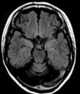

Chronic arteritis

Arteritis is the inflammation of the walls of arteries, usually as a result of infection or autoimmune response. Arteritis, a complex disorder, is still not entirely understood. [Source: Wikipedia ]